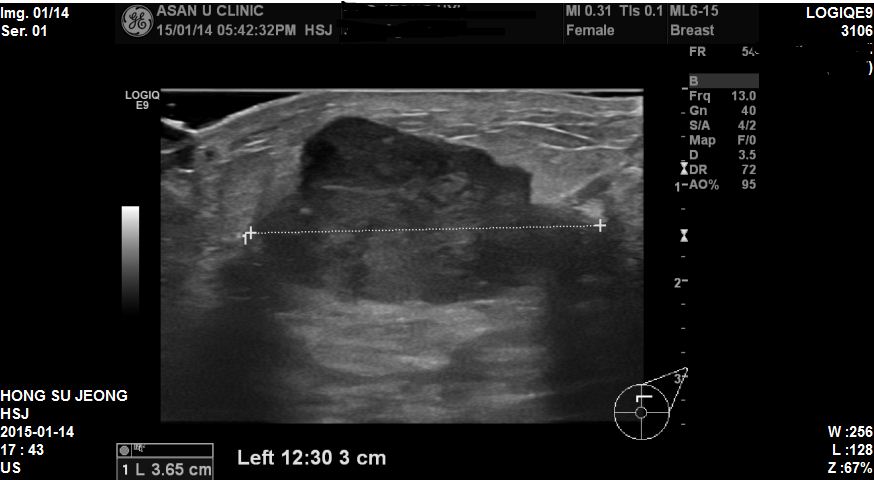

좌측유방에 만져지는 혹으로 내원하신 48세 환자분이십니다.

본원에서 왼쪽 12 : 30방향에 3.65cm 혹 조직검사하였고

결과상 침윤성유방암 진단되었습니다. 겨드랑이 전이까지는 되지않았지만

혹이 워낙에 커서 수술전 항암치료가 먼저 필요한 상황이여서

더 안타까웠습니다.